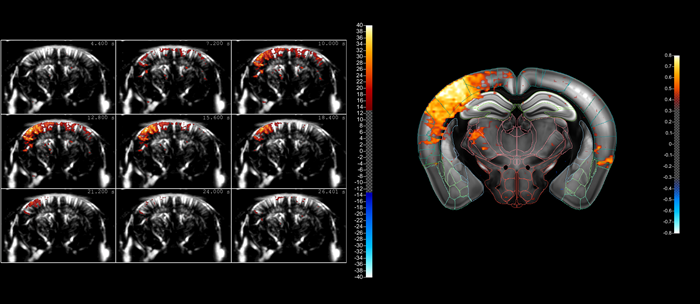

Indicative comparison of the imaging performance that can be achieved using cUS (left) and true fUS (right) for the rat brain (here involving a craniotomy), in both cases carried out by adjusting the scan settings on Iconeus One. fUS clearly has an advantage over cUS in terms of resolution and sensitivity. Image Credit: Iconeus